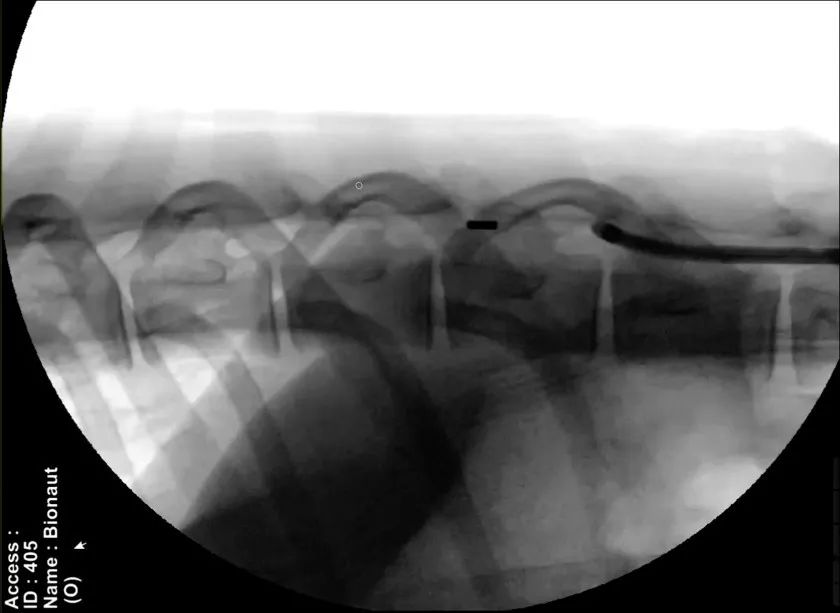

具体而言,该公司会在其首次临床试验中把装载着治疗药物的微型机器人注射到脊柱中,并使用一组位于头部和颈部周围的磁铁产生的磁场将机器人引导进入脑部患病区域。在到达正确的位置后,另一个磁信号将激活机器人药物舱的开关,释放药物。药物卸载后,医生再引导机器人返回至起始点,将其从脊柱处接离。

图 | Bionaut 微型机器人进入活羊的蛛网膜下腔(来源:Bionaut Labs 官网)

Shpigelmacher 进一步解释道,目前的技术已经允许机器人制造得足够小,但为了确保其能够在 X 光下实时清晰可见、方便追踪和操控,Bionaut 将微型机器人的大小尽可能保持在 1 毫米左右。